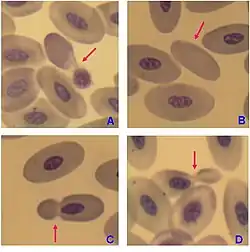

- The malaria parasite spends part of its life-cycle in red blood cells, feeds on their hemoglobin and then breaks them apart, causing fever. Both sickle-cell disease and thalassemia are more common in malaria areas, because these mutations convey some protection against the parasite.

Many diseases involving red blood cells are diagnosed with a blood film (or peripheral blood smear), where a thin layer of blood is smeared on a microscope slide. This may reveal poikilocytosis, which are variations in red blood cell shape. When red blood cells sometimes occur as a stack, flat side next to flat side. This is known as rouleaux formation, and it occurs more often if the levels of certain serum proteins are elevated, as for instance during inflammation.